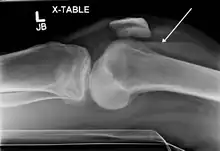

Lipohemarthrosis (presence of fat and blood from bone marrow in the joint space after an intraarticular fracture) seen on X-ray in a person with a subtle tibial plateau fracture

Lipohemarthrosis due to a tibial plateau fracture